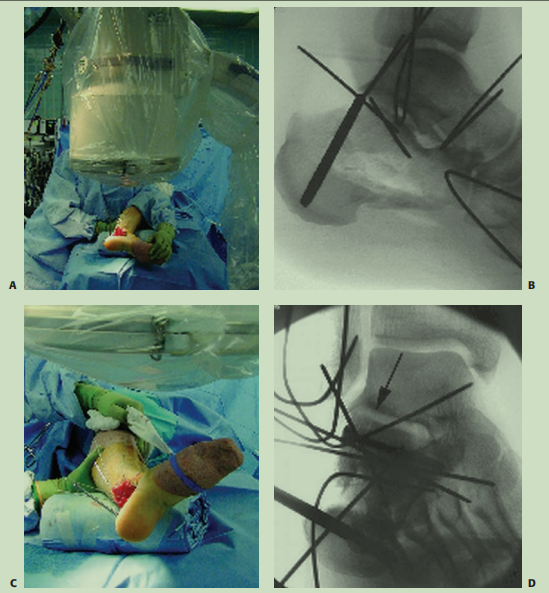

大L型切口,克氏针牵拉撬拨复位内翻畸形,D图的临时克氏针固定内翻畸形这个技巧很重要,最后复位关节面。F、G图显示术后透视可见解剖复位。

还是首先介绍了大L切口,图D展示了后足内翻的纠正方法。

术后轴位片显示了后足内翻的纠正,载距突螺钉的方向和长度值得学习。但图B选择克氏针穿过距骨来进行临时固定是否恰当,这个由各位同仁自己评判。